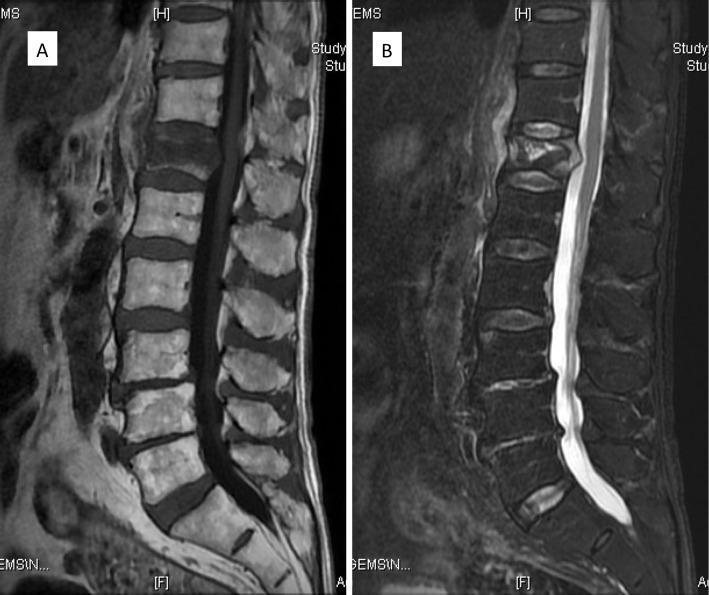

Percutaneous vertebral augmentation techniques, such as balloon kyphoplasty (BKP) and vertebral body stenting (VBS), are commonly used for surgical intervention in osteoporotic vertebral fractures (OVFs). However, markedly unstable OVF cases require additional fixation procedures, prompting the exploration of combined percutaneous vertebral augmentation and posterior fixation. A novel surgical approach involving percutaneous vertebral augmentation with upward penetrating endplate screws (PES) and downward PES, complemented by a short fusion of one above one below, was developed. This study aimed to introduce and report the preliminary outcomes of this technique based on a retrospective analysis of 20 consecutive cases in the short and medium term.

METHODS

Surgical indications are a vertebral wedge angle difference of 10° or more, vertebral pedicle fractures, posterior wall fractures, and diffuse low-signal changes exceeding 50% on T1-weighted magnetic resonance imaging. The procedure is reserved for highly unstable cases following a comprehensive health assessment. The surgical technique involves prone positioning, fluoroscopy-guided percutaneous vertebral augmentation, and the use of downward PES in the cranial vertebral body and upward PES for the caudal vertebral body by percutaneous technique. The fixation range is one above and one below.

经皮椎体强化技术,如球囊椎体后凸成形术(BKP)和椎体支架置入术(VBS),常用于骨质疏松性椎体骨折(OVF)的手术干预。然而,明显不稳定的OVF病例需要额外的固定程序,这促使人们探索经皮椎体强化与后路固定相结合的方法。一种新的手术方法应运而生,该方法包括经皮椎体强化联合向上穿透终板螺钉(PES)和向下的PES,并辅以相邻椎体间的短节段融合。本研究旨在通过对20例连续病例的短期和中期回顾性分析,介绍并报告该技术的初步结果。

方法

手术适应证为椎体楔角差10°或以上、椎弓根骨折、后壁骨折以及T1加权磁共振成像上超过50%的弥漫性低信号改变。该手术仅适用于经过全面健康评估的高度不稳定病例。手术技术包括俯卧位、透视引导下的经皮椎体强化,以及通过经皮技术在头侧椎体使用向下的PES,在尾侧椎体使用向上的PES。固定范围为相邻椎体。